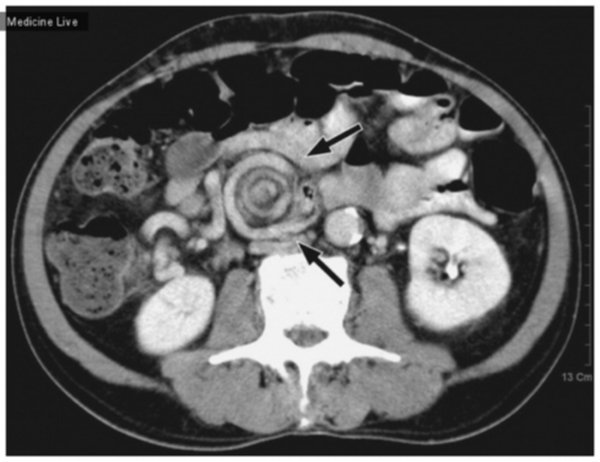

Кт слепой кишки

Кт слепой кишки 112 фото